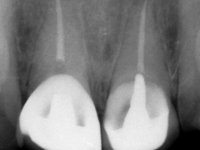

Male patient, 45 years old, smoker, with oesophageal reflux and poor oral hygiene. Teeth 11 and 21 presented an endodontic treatment and tooth 21 was rehabilitated with a Richmond type crown done 12 years ago. Tooth 11 presented an extensive restoration in composite resin in the buccal surface bonded exclusively to dentin. The palatal surface presented acid erosion and an extensive reconstruction in the endodontic access. The clinical crown was 4,5mm height and the root had 11mm.

After a previous dental impression in silicone to construct a provisional crown with the original shape, a tooth preparation was done following the principles of the Richmond crown. The intra-coronal preparation was done only until the enamel-cement line, without including the root.